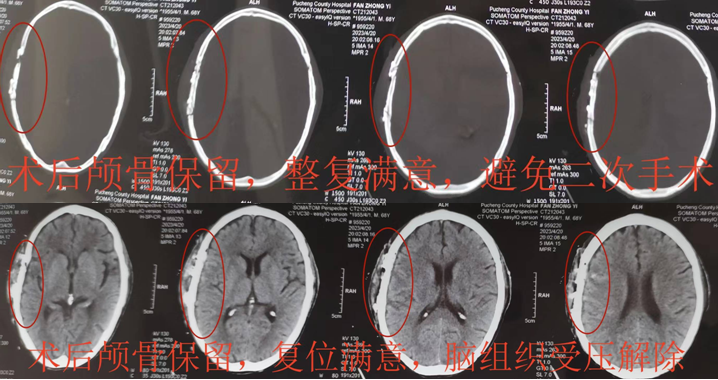

训给了刘晓斌坚定的信念,经过近2小时认真仔细的操作,原本支离破碎的颅骨被完全整复,患者自体颅骨不仅得到保留,同时避免了二次颅骨修补手术的风险,也极大地节省了医疗费用。手术取得圆满成功,术后患者很快清醒,伤口愈合良好,神经功能恢复顺利,复查头颅CT显示颅骨整复塑型良好。